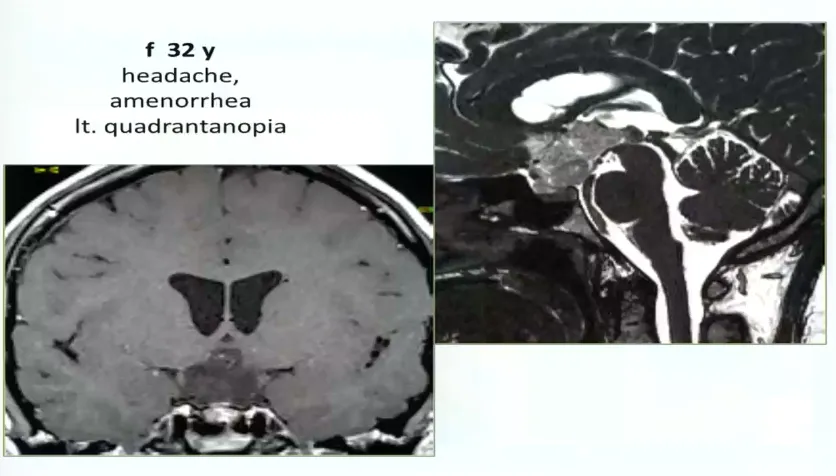

32岁女性,头疼、闭经、视野缺损,左侧视野象限盲,累及视路后部、下丘脑,脚前窝。病变完全位于中线,因此采用前纵裂入路。手术最终顺利全切。

图:术前MRI

术中情况:病变完全位于中线入路,因此采取前纵裂入路。

术后情况:手术做的非常漂亮,解剖性全切,无神经损伤。